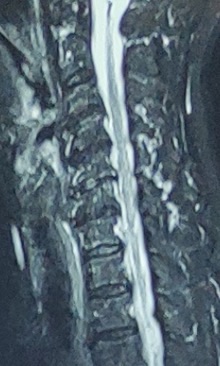

图2 一位80岁老太太颈椎核磁,无神经症状,但每一节都有增生突出表现。

老伴俩同意了做颈椎核磁检查,放射科第二天就做好了核磁,第三天放射科报告刚出来,他们就一起又来到了同一个专家门诊的诊室。这回王大爷知道自己是外行,就主要由张老太询问情况。老太太看到报告上面描述了“颈椎C3-C7都有不同程度的突出”,非常的担心:“我的颈椎是不是非常严重,每一节都有突出的话要不要都开刀割掉?”

医师仔细的阅读了她的核磁片子,微笑的回答他:“不是这样的,您看到的报告单只是影像学上形态的描述,它不是决定治疗方式的临床诊断,必须要经过临床症状、体征和影像相印证才能决定进一步的治疗方案。您的症状是典型的单一神经根受压引起的,应该是颈椎67节椎间盘有一处突出增生压迫了您的颈椎神经根。”

“上次和您讲过人到中年开始颈椎开始出现退变增生,颈椎椎间盘会不同程度的出现脱水、塌陷,椎间盘后缘出现膨隆、突出,同时伴随着椎体周边的骨质增生,椎管后面的黄韧带肥厚,颈椎椎管出现逐渐进展的狭窄。这是一个缓慢发展的过程,由于颈椎椎管本身空间比较大,轻度的狭窄增生就算碰到了脊髓神经,脊髓神经还是有空间让开,所以并不是出现了增生突出就一定有神经压迫,大多数颈椎的突出就是人老化的表现,很多人是没有症状的,或者是颈部软组织的劳损疼痛,完全可以通过自身保健或保守治疗缓解减轻疼痛症状。但是如果在退变狭窄的基础上,如果出现椎间盘纤维环破裂,髓核突出,或者颈椎的增生狭窄不断发展严重到一定程度,神经再也没有空间,出现明确的神经压迫,就会出现非常典型的神经根性疼痛,或者脊髓压迫出现四肢麻木乏力。这时候就必须要手术治疗了。”

“那现在我片子上有这么多节的突出,到底哪一节是我的引起症状的节段呢?”张老太还是有疑惑。

医生继续耐心的解释:“神经根型颈椎病一般都是颈椎侧方突出或狭窄压迫单一神经根引起,因此仔细读片明确定位诊断,确定您病症的真正病因,也就是医生所说的责任节段是非常重要的。您的症状和片子都支持C67节段侧方存在神经根明显的压迫,C6-7是您的责任节段。某种意义上说,只有把脊柱的病症定位到节段、明确压迫的性质,才是真正的诊断,而不是把一切都套上颈椎病。”